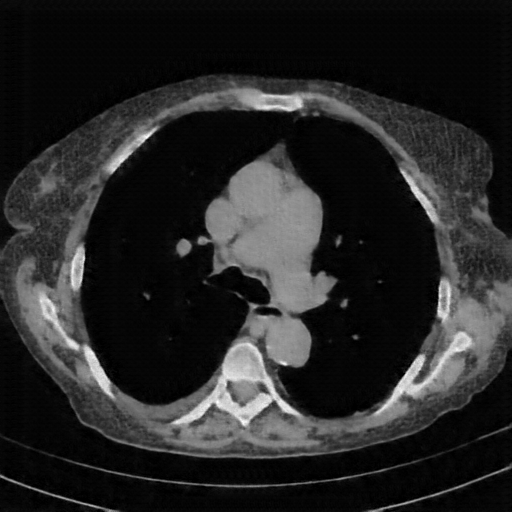

Generated VENOUS CT scan (A→B translation)

Full window (WL 1023.5, WW 4095 β†’ Low βˆ’1024, High +3071)

Actual HU range: [-1024.0, 847.3]